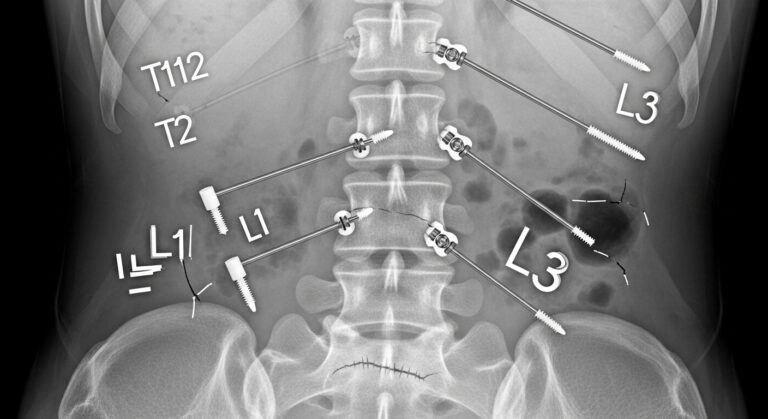

Introducción Las lesiones en la columna vertebral son una de las principales causas de dolor crónico y discapacidad en personas de todas las edades. Estas